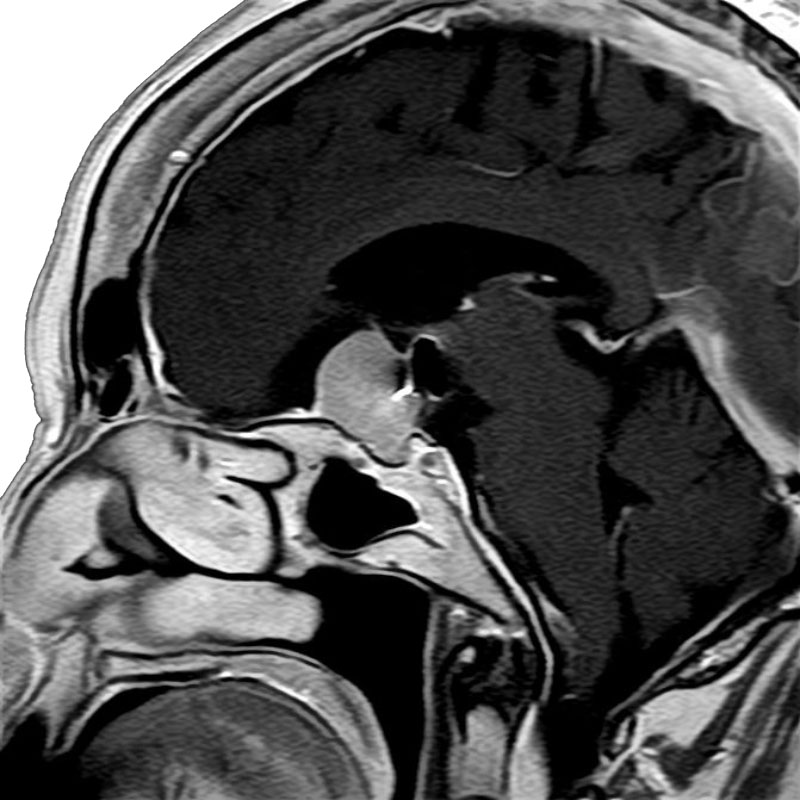

脳動静脈奇形

血管塞栓術

松田/濵田/元永